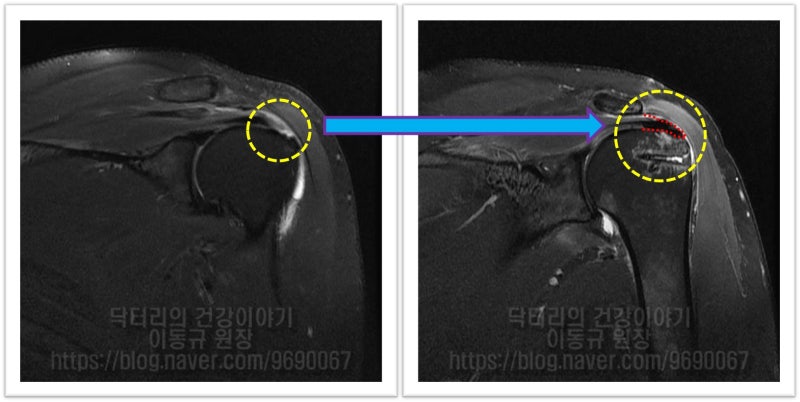

이 환자의 경우 나이가 비교적 젊음에도 불구하고 힘줄의 상태가 매우 좋지 않았습니다. 아마 수년간 통증주사(아마도 스테로이드)만 맞고 팔을 계속 사용하면서 회전근개 손상은 점점 진행되고 퇴행성 변화가 가속화 된 것으로 사료됩니다. 수술 후 6주에 MRI 검사를 시행하였습니다.

어깨 회전근개 파열은 진행하는 질환입니다. 어떠한 질환도 그렇듯이 초기에 치료를 하는 것이 가장 빠르게 낫고 결과도 좋습니다. 병이 진행하게 되면 치료하는 것도 더 커지거나 많이지게 됩니다. 결과 역시 초기보다 좋지 않을 수도 있습니다. 병이 진행되었다 하더라도 상기와 같이 치료할 수 있는 방법이 있으니 병이 많이 진행되었더라도 걱정할 필요는 없겠으나 그래도 초기에 치료하는 것이 무엇보다 중요합니다.